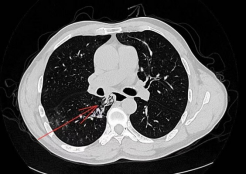

该研究中的患者彭先生因“发现食管气管瘘20余天”到我院治疗。彭先生两年出现反复咳嗽、咳黄脓痰,当地医院就诊后诊断为“肺脓肿”,予抗感染对症治疗后,黄脓痰转向白痰,20余天前彭先生出现咳血,遂至外院查胸部CT,结果提示:食管-右肺下叶背段纵隔旁支气管瘘。

彭先生到我院心胸外科完善相关检查,明确诊断,排除手术禁忌后行单孔胸腔镜下食管气管瘘修补术,手术时间3小时。术后1周复查造影,未见造影剂外漏。术后9天彭先生就开始进口进食了。术后11天康复出院。